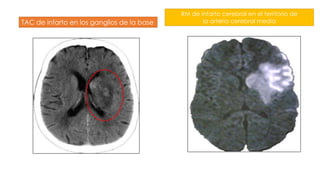

El cuerpo calloso es localización común de estas lesiones (20%), especialmente el

esplenio, que puede acompañarse de hemorragia intraventricular, en cuyo caso

puede ser la clave para el diagnóstico en TC.

Fig (32).Zona hiperintensa del cuerpo calloso en difusión/http://www.scielo.cl